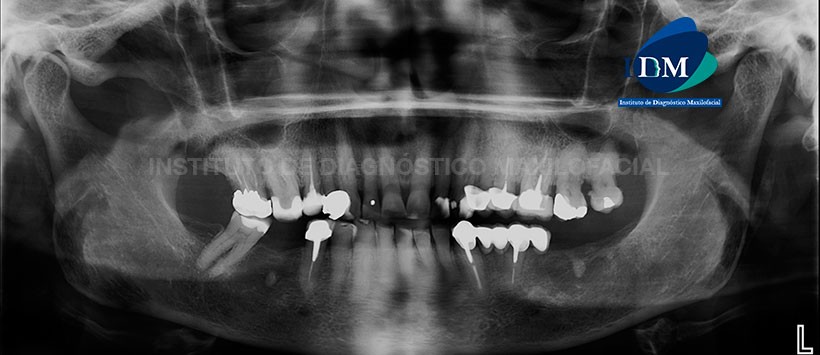

A la evaluación de la radiografía panorámica se pudo apreciar mineralización de ambos procesos estilohioideos, neumatización alveolar y engrosamiento de la mucosa basal de ambos senos maxilares, apiñamiento y faceta de desgaste coronario del sector dentario anterior (atrición), leve reabsorción ósea alveolar bimaxilar, ausencias de piezas dentarias, así como múltiples restauración y piezas con material de obturación de conductos. Sin embargo, en la pieza 26 se puede evidenciar material de obturación en las raíces palatina y distovestibular mientras que en la raíz mesial se puede evidenciar la ausencia de material de obturación juntos con un proceso osteolítico apical. Adicionalmente se aprecia un espigo metálico interradicular con corona protésica la cual tiene una ligera falta de sellado cervicodistal.

En la pieza 27 y 28 se evidencio presencia de un aumento de la densidad perirradicular, placa dental mineralizada en zona cervical y material de restauración coronario. (Figura 1)